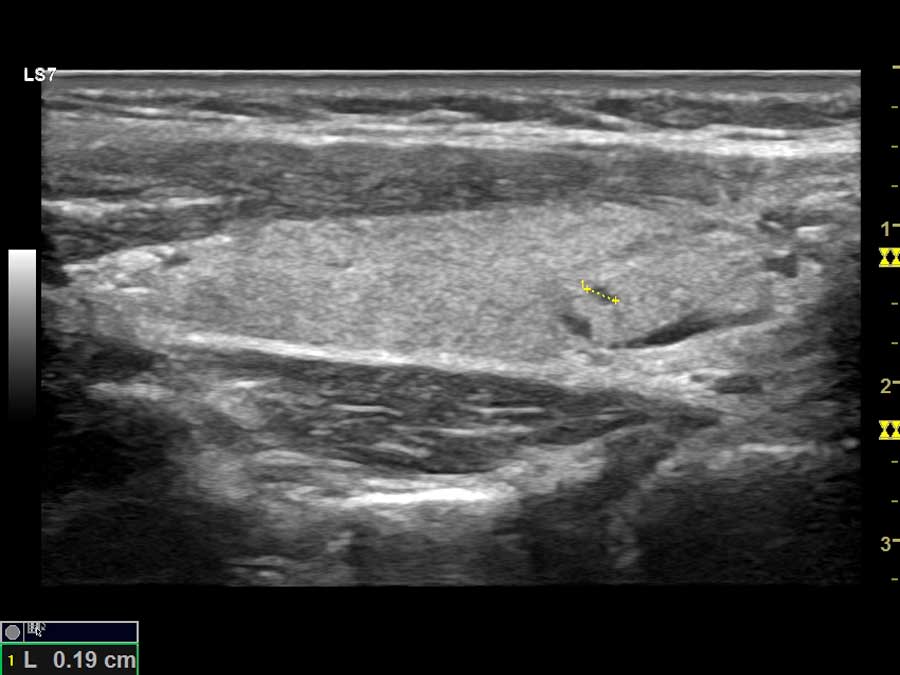

- Υπερηχογράφημα καρωτίδων (υπολογισμός μέσου όρου ΙΜΤ)